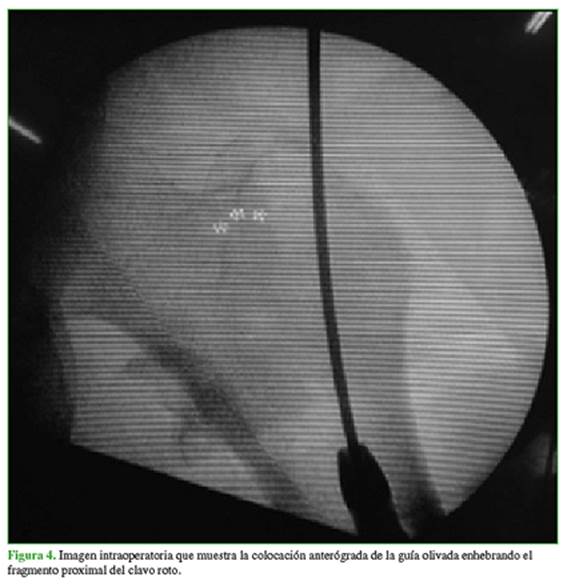

Para extraer el fragmento proximal se usó un abordaje de 3 cm proximal al trocánter mayor. Se colocó una clavija guía de 3,8 mm roscada y, bajo control radioscópico, se realizó un correcto punto de ingreso. Se retiró la clavija guía y luego se introdujo la guía olivada por su extremo no olivado. El objetivo de esta técnica es enhebrar y lograr el atascamiento de la oliva en el extremo proximal del implante (Figura 4). La guía olivada se debe avanzar desde el trocánter mayor hasta el abordaje del fémur distal para hacer la extracción en forma retrógrada y segura, a través del abordaje transrotuliano.